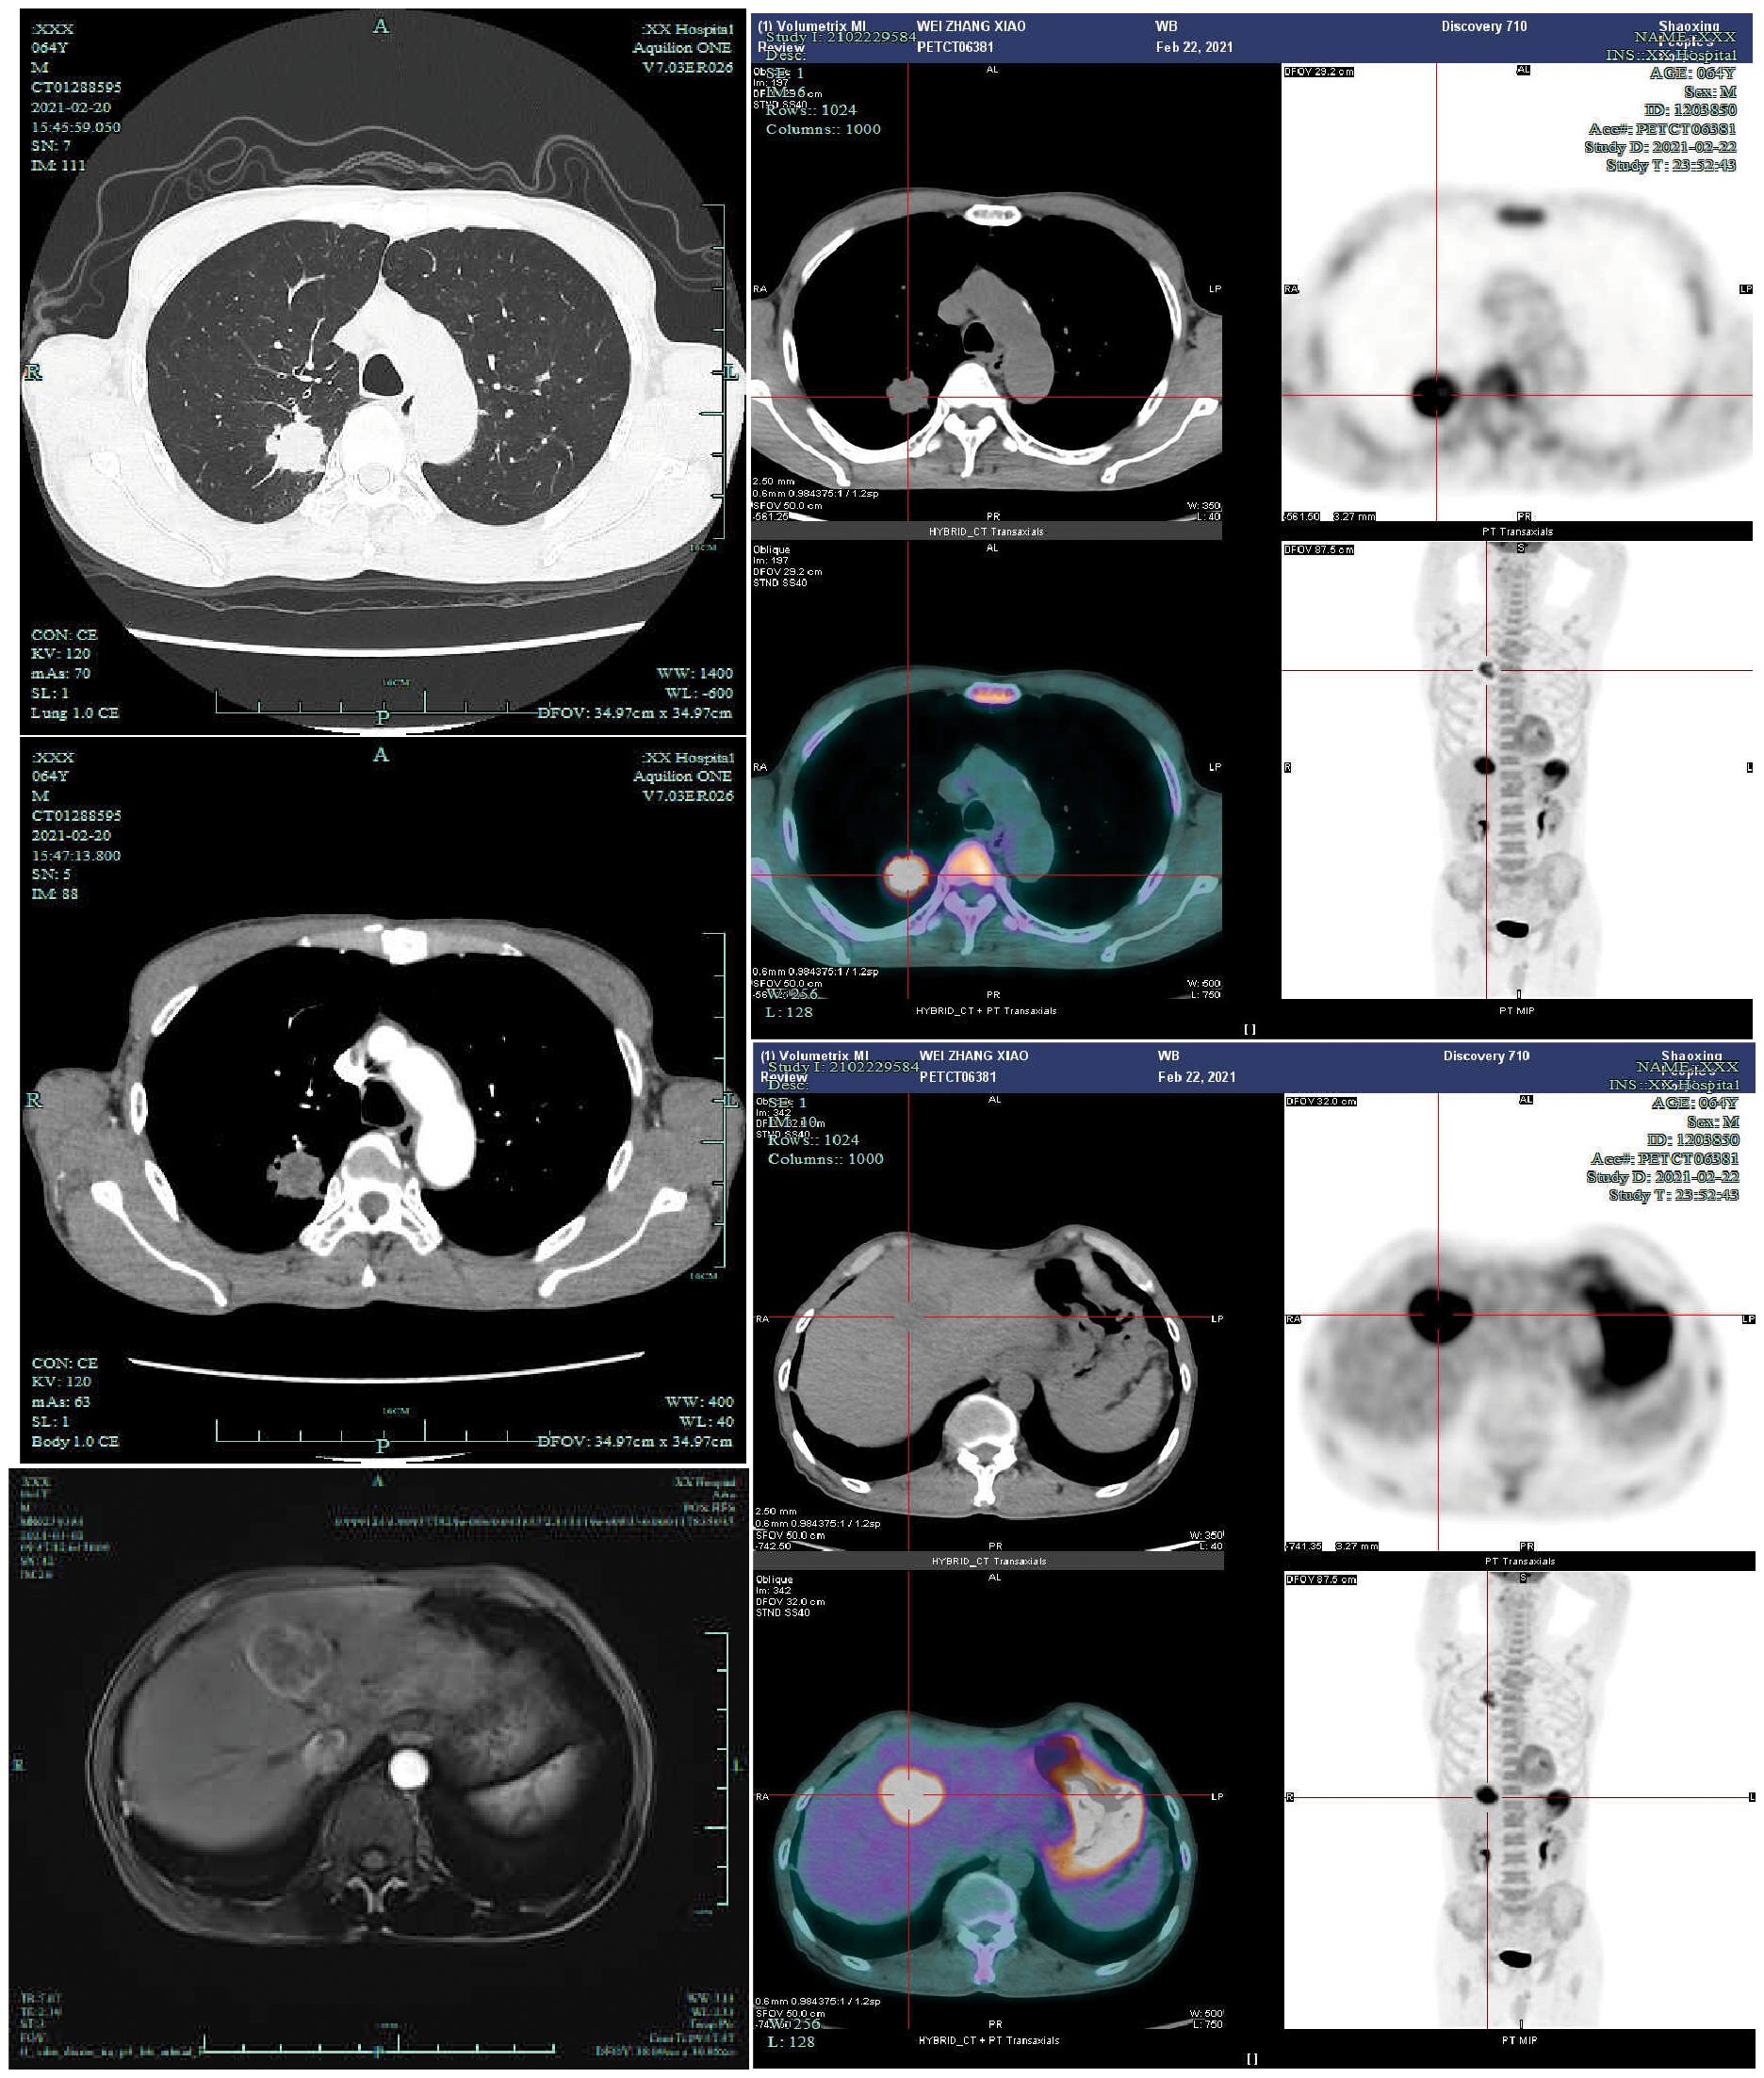

A 64-year-old male was admitted to the Department of Respiratory Medicine at our hospital on February 20, 2021, due to the presence of a right upper lung nodule first identified more than two years earlier. The nodule was initially detected on chest CT imaging two years prior to admission and was found to have progressively enlarged during subsequent regular follow-up examinations(historical imaging unavailable due to prolonged interval). The patient denied respiratory symptoms (cough, sputum, chest pain), constitutional symptoms (low-grade fever, night sweats), or abdominal/neurological complaints. Medical history included chronic bronchitis (untreated) and a 40-pack-year smoking history (current smoker, 30 cigarettes/day), with no alcohol use or family history of malignancies. On February 20, 2021, a contrast-enhanced chest CT scan performed after admission revealed a solid nodule in the posterior segment of the right upper lobe, measuring approximately 28 × 32 mm, with a CT value of about 25 Hounsfield units. The nodule exhibited a lobulated margin with surrounding spiculation and demonstrated moderate enhancement following contrast administration. The incidental detection of a hepatic space-occupying lesion on chest CT raised suspicion of metastatic disease, prompting subsequent abdominal Magnetic Resonance Imaging (MRI) evaluation. Contrast-enhanced abdominal MRI demonstrated a 38×40 mm round lesion in segment IV of the left hepatic lobe, showing hypointensity on T1-weighted imaging and heterogeneously hyperintense signal on T2-weighted imaging, radiologically consistent with metastatic involvement. PET-CT revealed increased Fluorodeoxyglucose (FDG) uptake in both the right upper lung nodule (SUVmax=8.30) and hepatic lesion (SUVmax=11.89 on conventional imaging, increasing to 13.00 on delayed imaging) (Figure 1), further supporting the diagnosis of metastatic disease. Serum tumor markers including carcinoembryonic antigen (CEA) and Alpha-fetoprotein (AFP) were within normal limits, and routine blood tests, biochemical profiles, and cranial MRI showed no significant abnormalities. Pathological examination of CT-guided percutaneous needle biopsy specimens from the pulmonary nodule confirmed squamous cell carcinoma (Supplementary Figure 1).

Figure 1

Figure 1. Upon admission, the patient underwent contrast-enhanced chest CT(2021-2-20), contrast-enhanced liver MRI(2021-3-2), and PET-CT examinations(2021-2-23). PET-CT demonstrated a right upper lung nodule with a maximum standardized uptake value (SUVmax) of 8.30, and a liver mass with SUVmax of 11.89 on conventional imaging and 13.00 on delayed-phase imaging.